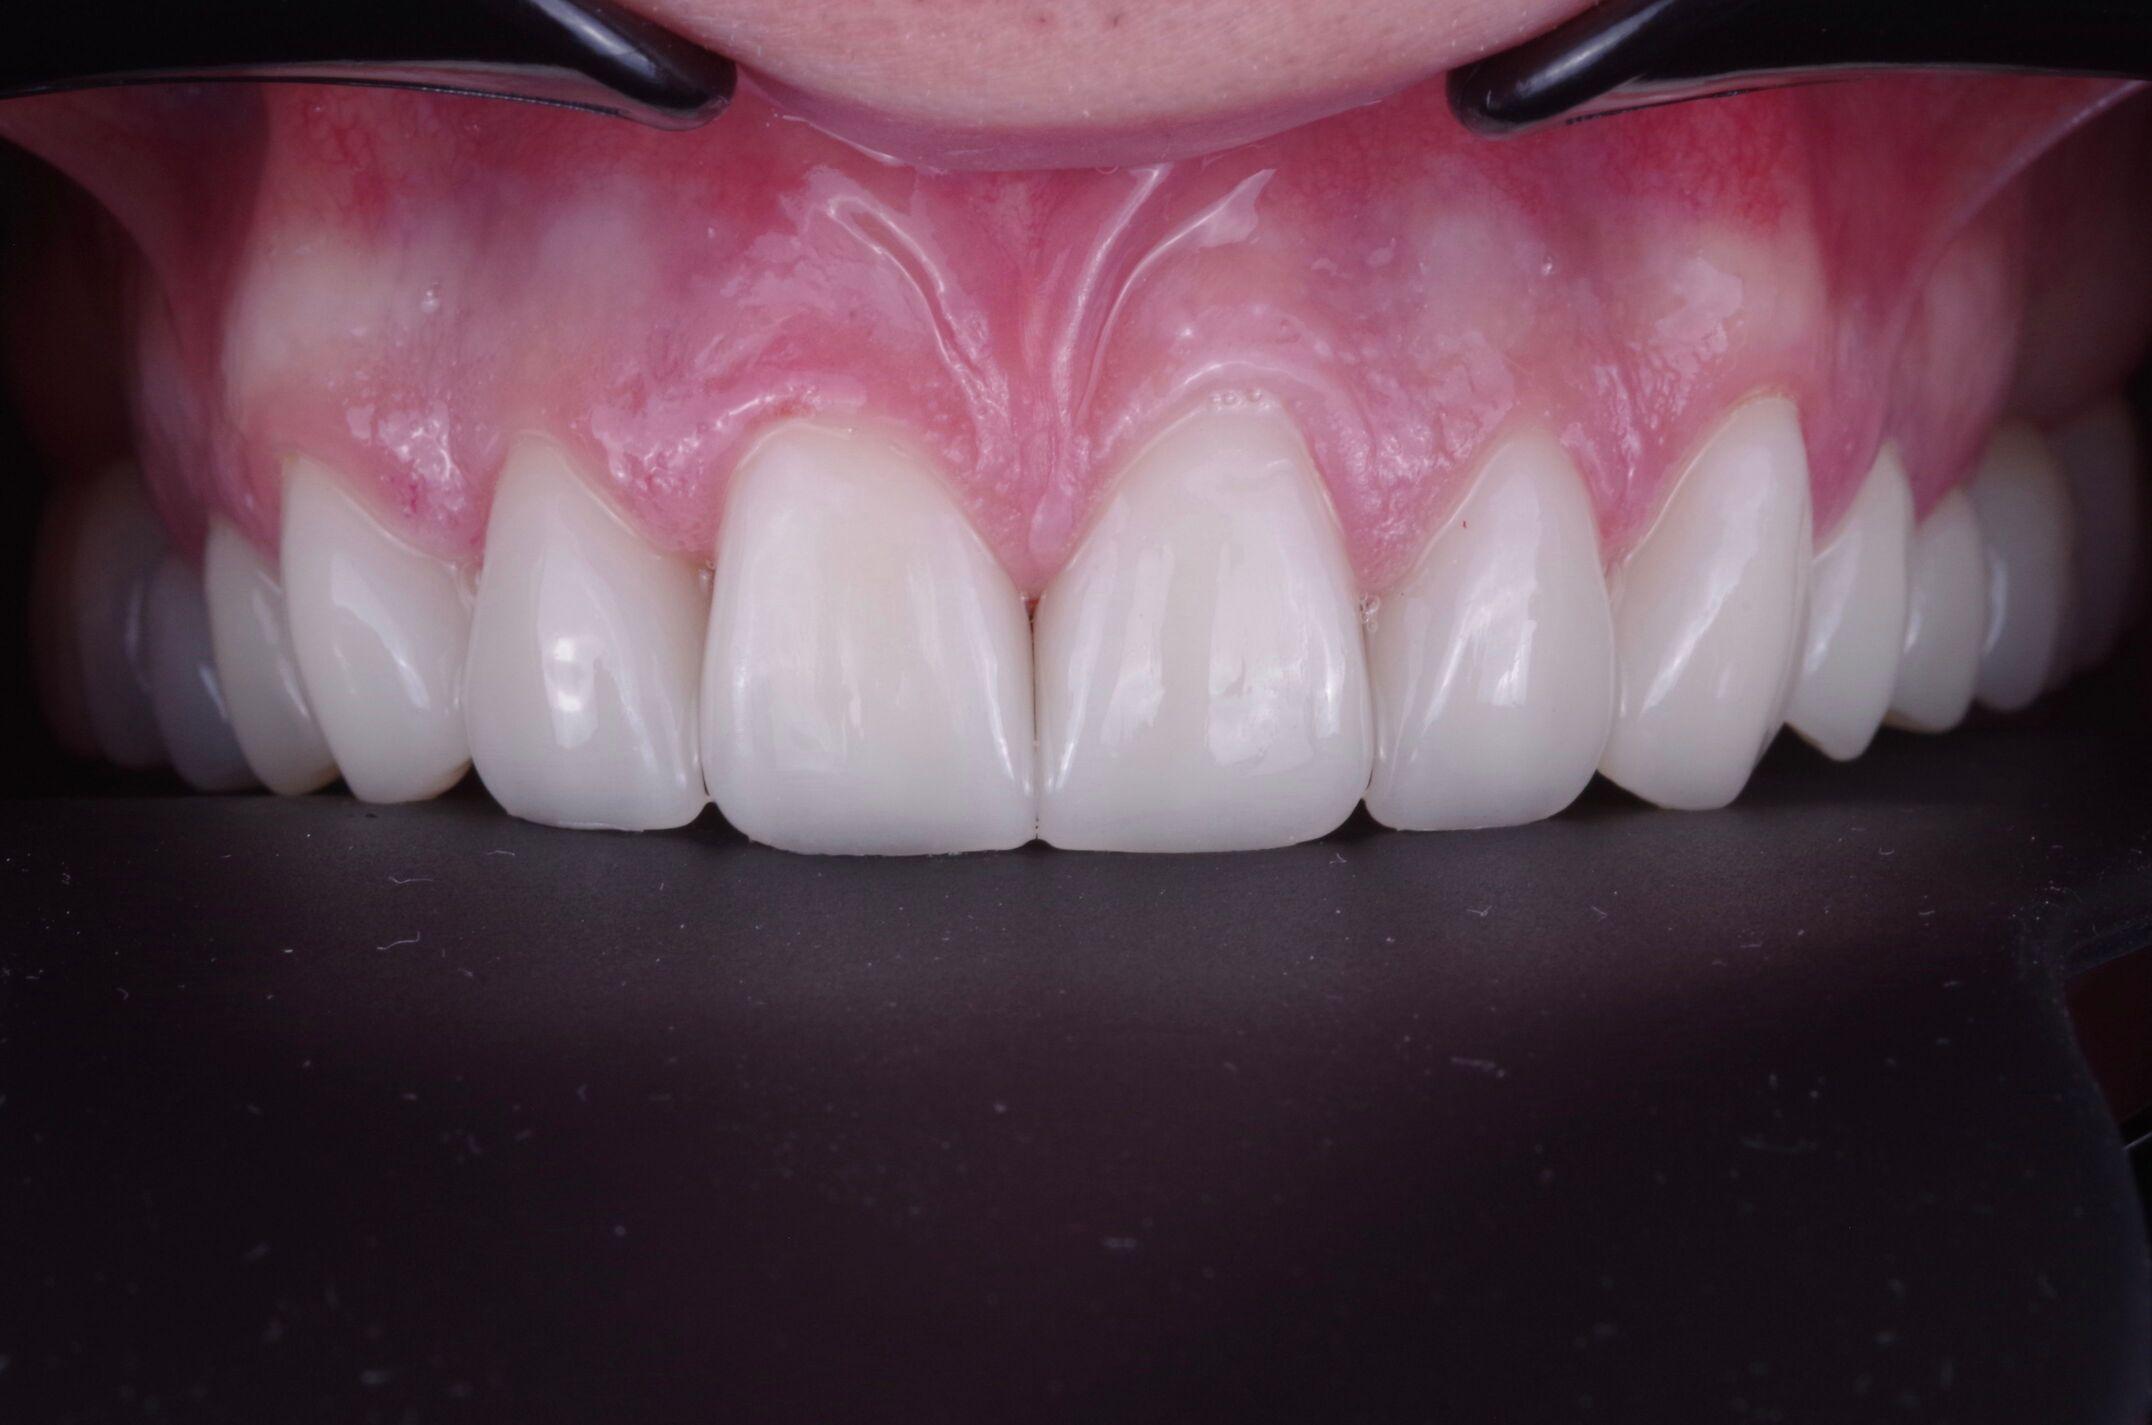

Мы используем ультратонкие прессованные керамические виниры последнего поколения – инновационное решение, которое обеспечивает идеальную эстетику и максимальную естественность. Благодаря современным технологиям мы добиваемся безупречного результата, сохраняя здоровье зубов и минимизируя необходимость обточки.

Высокая эстетика

Виниры имитируют естественный блеск и прозрачность эмали, создавая эффект «своих зубов».

Долговечность

Керамические виниры служат более 15 лет без потери цвета и оттенка.

Мгновенный эффект

Новая улыбка уже через 5–7 дней после начала лечения.

После установки виниры полируются для достижения идеальной гладкости и естественного блеска.